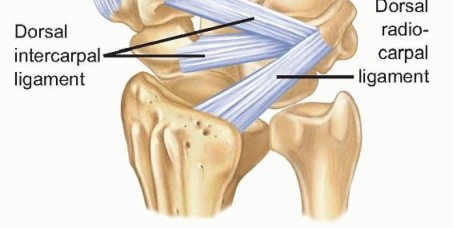

The trapezium and triquetrum similarly possess specialized anatomical features that dictate their fracture patterns and surgical management. The trapezium features a prominent volar ridge, which, akin to the hamate hook, serves as the radial attachment for the transverse carpal ligament. Medial to this ridge lies a deep fibro-osseous groove that houses the flexor carpi radialis (FCR) tendon. Fractures of the trapezial ridge can lead to painful FCR tendinopathy or rupture. The triquetrum, situated on the ulnar aspect of the proximal row, is heavily tethered by the dorsal radiocarpal and dorsal intercarpal ligaments. Extreme wrist flexion and ulnar deviation can cause these robust ligaments to avulse a fragment of the dorsal triquetral cortex, resulting in the most common non-scaphoid carpal fracture. Understanding these specific ligamentous and tendinous associations is critical for interpreting fracture displacement and planning surgical approaches.